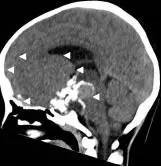

病例1:患儿男性,9岁。因反复出现意识丧失、视力降落半年收入院。入院后CT及 MRI显示颅内有形态不规则、“超大型”的颅咽管瘤,最大径约10厘米,见图1、图2。

图1.术前CT显示典型的囊性颅咽管瘤